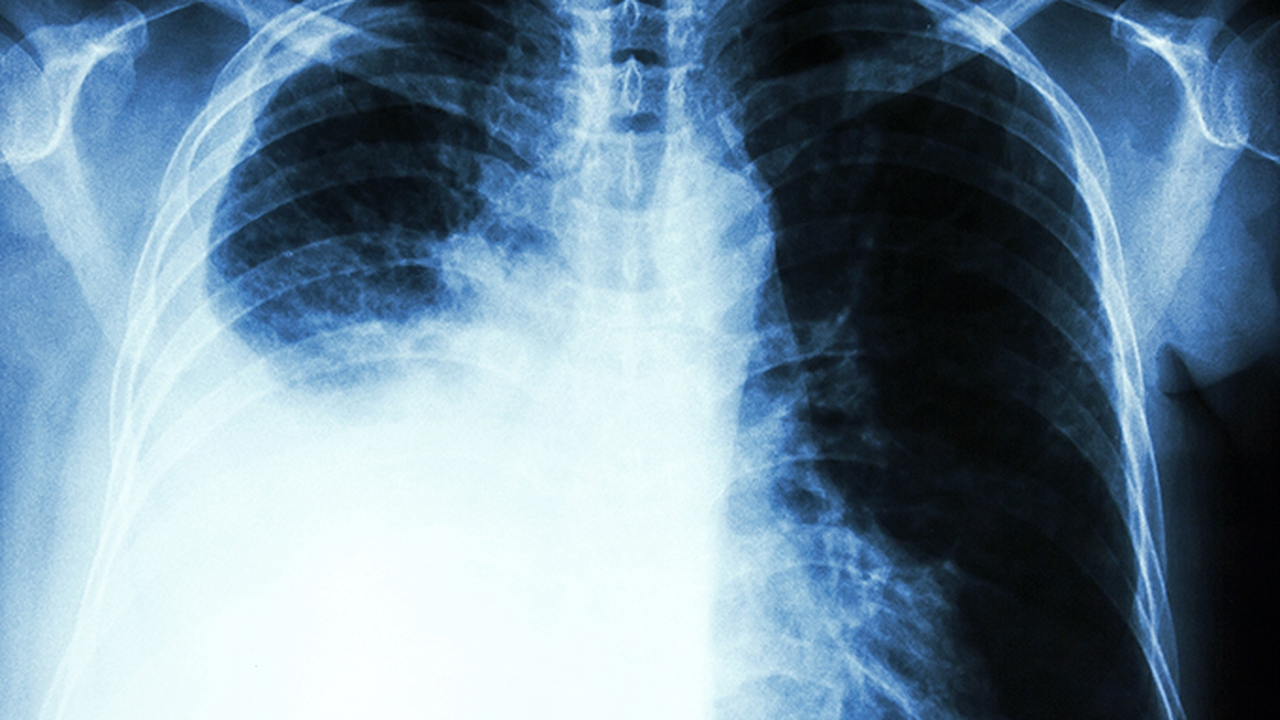

南京肺癌中醫(yī)治療醫(yī)院排名榜前十名

南京治療肺癌中醫(yī)特色突出的醫(yī)院包括江蘇省中醫(yī)院、南京中醫(yī)藥大學(xué)附屬醫(yī)院(江蘇省第二中醫(yī)院)、南京市中醫(yī)院、江蘇省中西醫(yī)結(jié)合醫(yī)院、東南大學(xué)附屬中大醫(yī)院中醫(yī)科等。這些醫(yī)院在肺癌的中醫(yī)藥調(diào)理、扶正祛邪及放化療輔助治療方面積累了豐富經(jīng)驗,部分醫(yī)院還開展中醫(yī)腫瘤??崎T診。